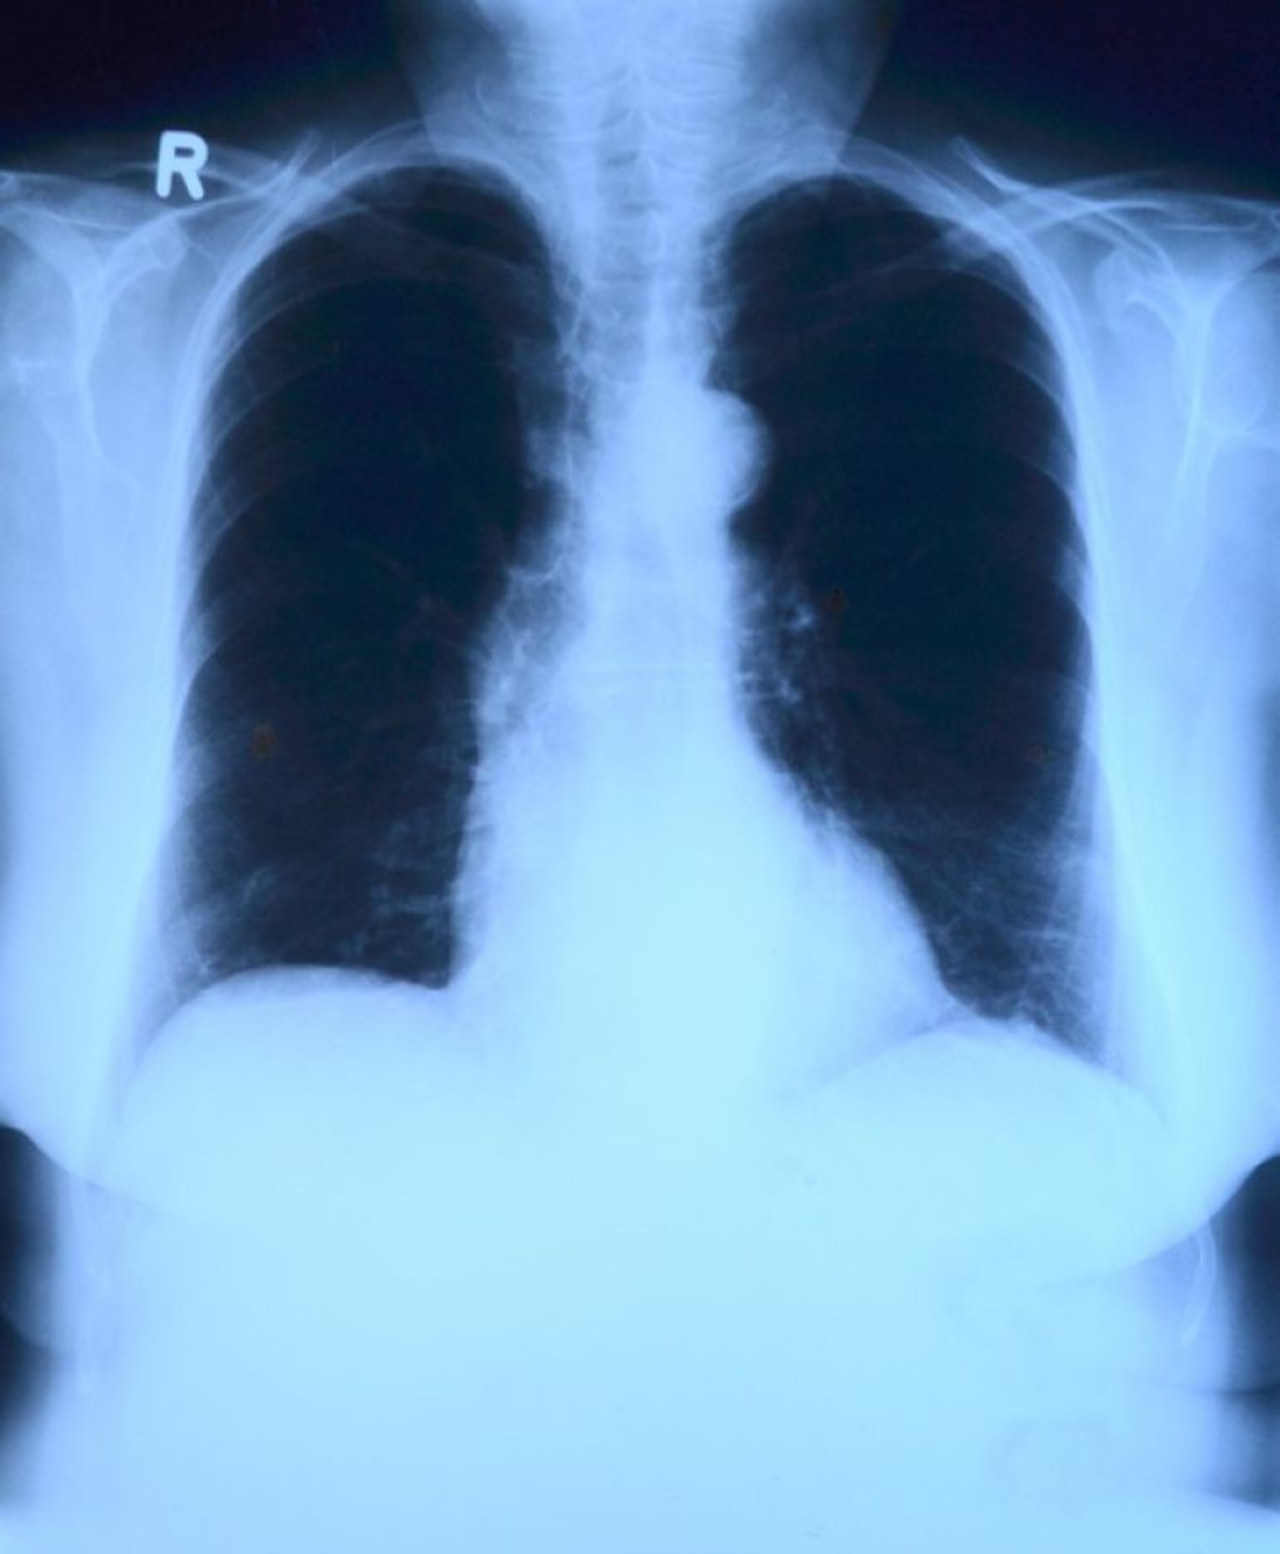

Badania, o których mowa to  specjalistyczny test IGRA, czyli badanie krwi i prześwietlenie klatki piersiowej. - Jeśli wynik badania będzie pozytywny, wówczas my zajmiemy się leczeniem tego pacjenta - zapewnia Youssef Sleiman.

Specjaliści przypominają, że gruźlica jest chorobą zakaźną. Wiele osób ją bagatelizuje i trafia na leczenie zbyt późno, w dodatku zaraża innych. - Ta choroba nie powoduje żadnych zmian osłuchowych nad płucami, dlatego lekarz badając pacjenta może stwierdzić, że jest on zdrowy. Dopiero dokładne badania mogą wykazać, czy mamy do czynienia z gruźlicą. Dlatego tak potrzebna jest kampania informacyjna i zachęcenie ludzi do badań i zwracania uwagi na sygnały, jakie wysyła organizm - informuje Youssef Sleiman.